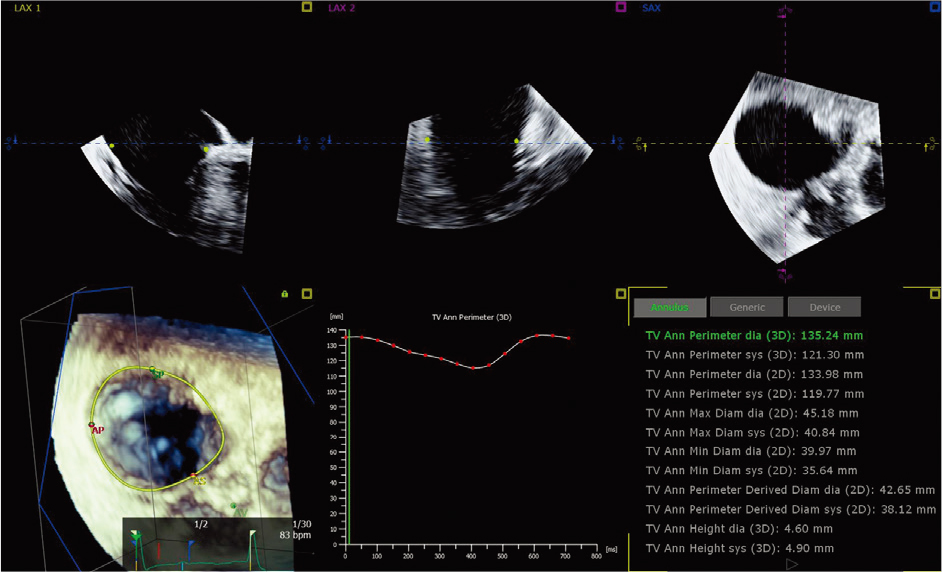

新的、先进的测量方法

借助AI-based的新功能和先进的自动化技术(例如我们的 3D 自动三尖瓣和彩色流量量化工

具),您可以实现更高的可重复性和更智能的工作流程,这样您的团队就可以减少在琐碎任

务上花费的时间,而将更多的时间花在挽救生命上。(来源:成贯仪器)

![]() 3D 自动彩色血流定量* 提供 AI 来快速、简单且可重复地测量二尖瓣反流 (MR) 体积,以帮助评估 MR 严重程度。 | ![]() 3D 自动三尖瓣定量* 人工智能通过精确的术中TV环测量(初始尺寸确定和CT计划)帮助确认/重新评估设备尺寸/选择。 |